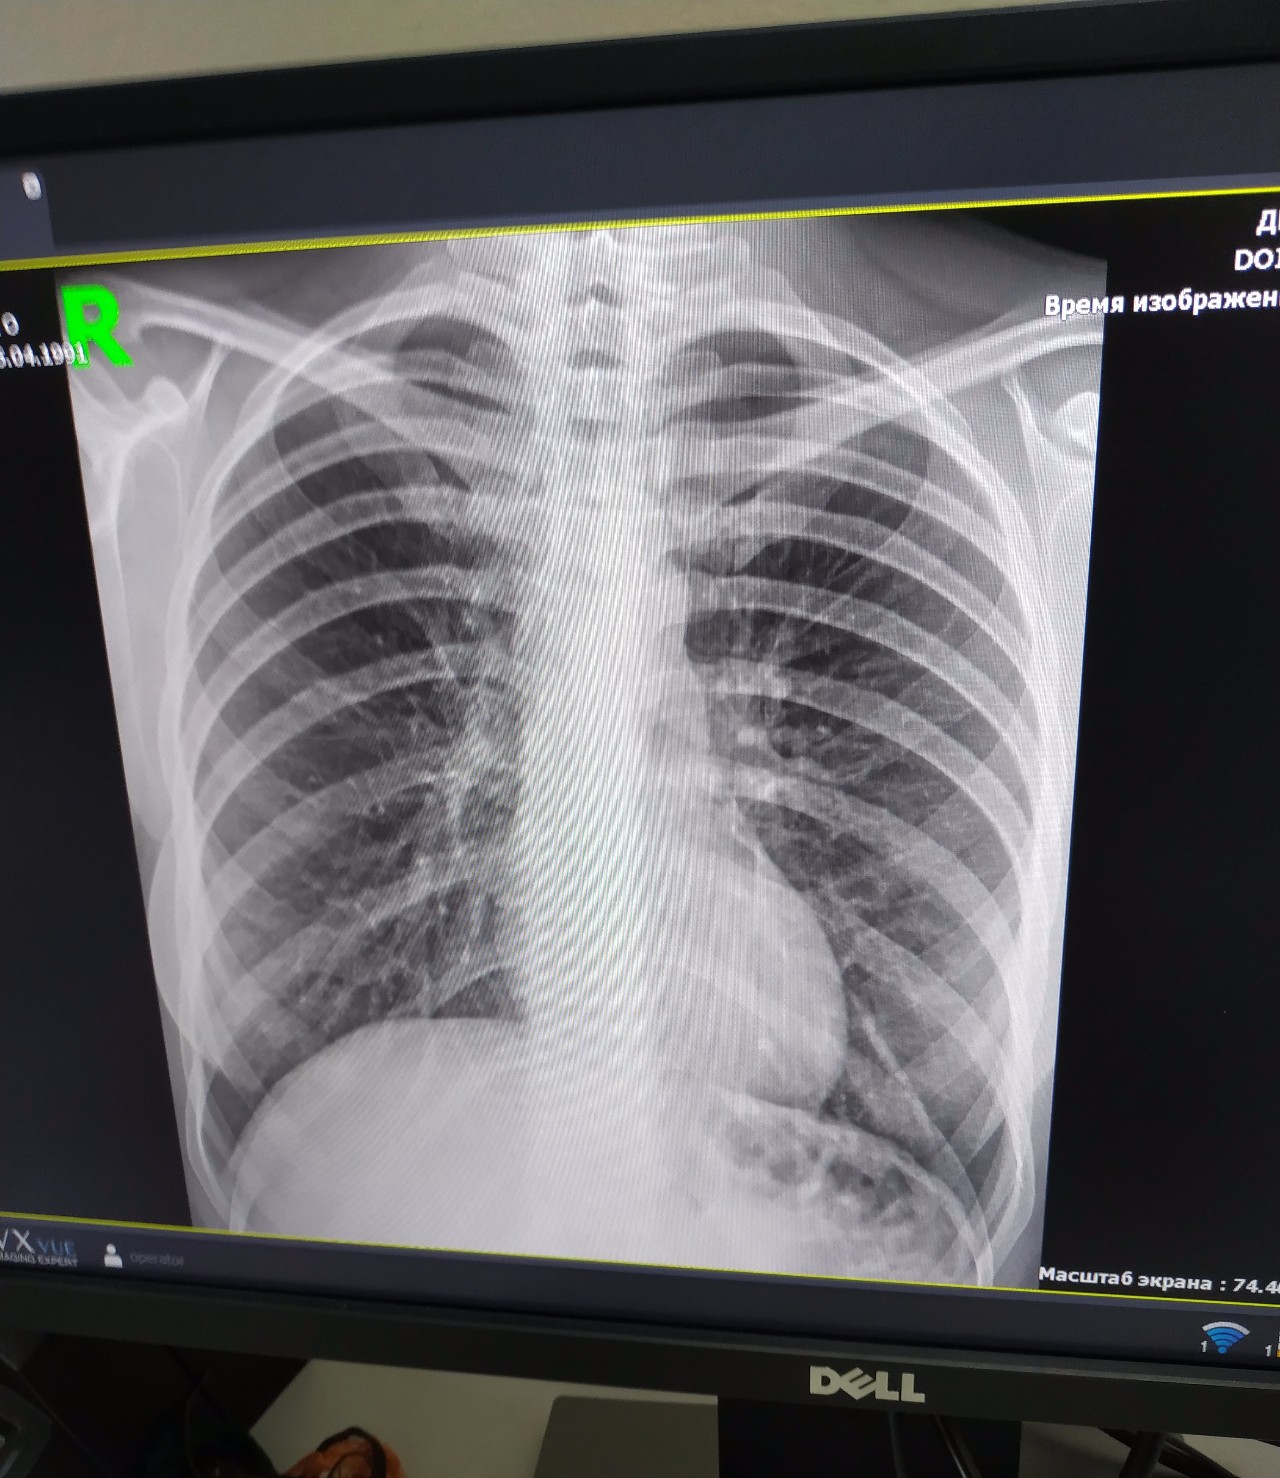

Рентген здоровых легких: примеры снимков и советы

Раздел: Сокровищница опыта